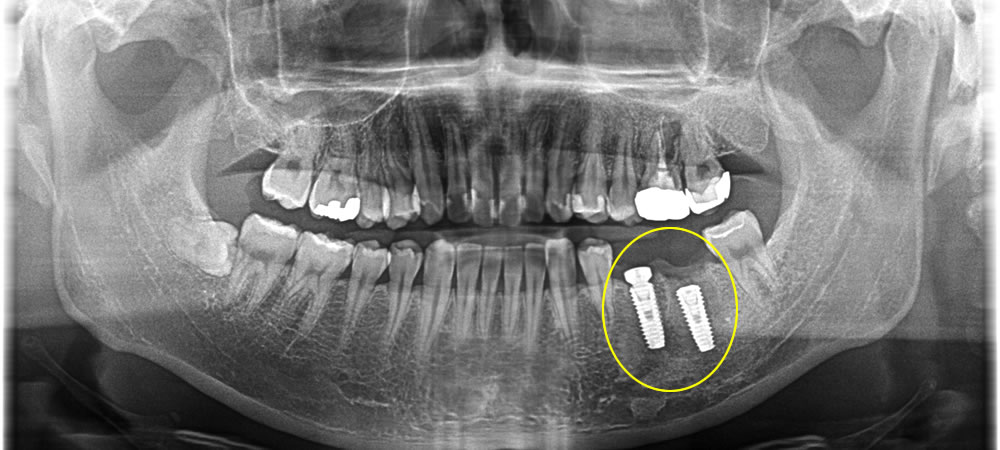

インプラント手術の実施

抜歯した部分に2本のインプラントを埋入し、骨造成も同時に行いました。